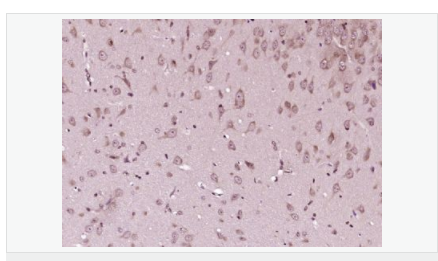

image.png